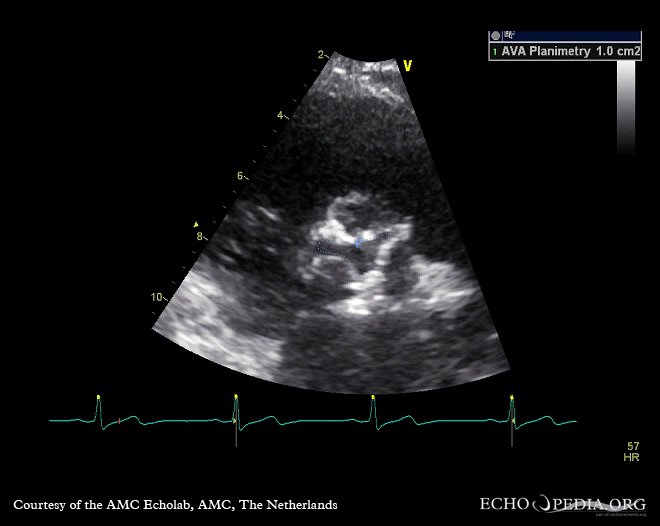

أما تأثير مرض الضغط المزمن على الصمامات فيظهر أكثر على الصمام الأبهر الذي يعاني من دفع الدم بقوة ويتصلب أسرع من المعتاد خصوصا في وجود سكر/تدخين/سمنة/كوليسترول عالي

تكلس الصمام قد يسبب تضيق أثناء الضخ وكذلك قد يمنع الصمام من الإغلاق بشكل كامل وبالتالي يسبب إرتجاع اثناء الانبساط